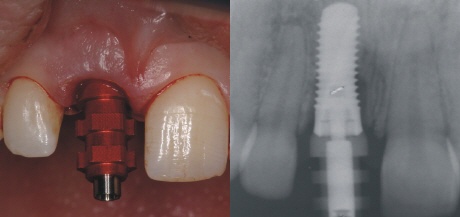

Sofortimplantation

Da in diesem Fall die Knochenstruktur komplett erhalten war, konnte in das Zahnfach direkt ein passendes Implantat eingebracht werden. Das linke Bild zeigt die optimale Positionierung, der Hilfspfosten (Einbringpfosten) des Implantates ist noch auf dem Implantat moniert.

Abformpfosten

Auf das Implantat wird ein sogenannter Abformpfosten montiert, mit dessen Hilfe man die Position des Implantates auf ein Gipsmodell übertragen kann. Der perfekte Sitz des Pfostens wird mit einem Röntgenbild kontrolliert.